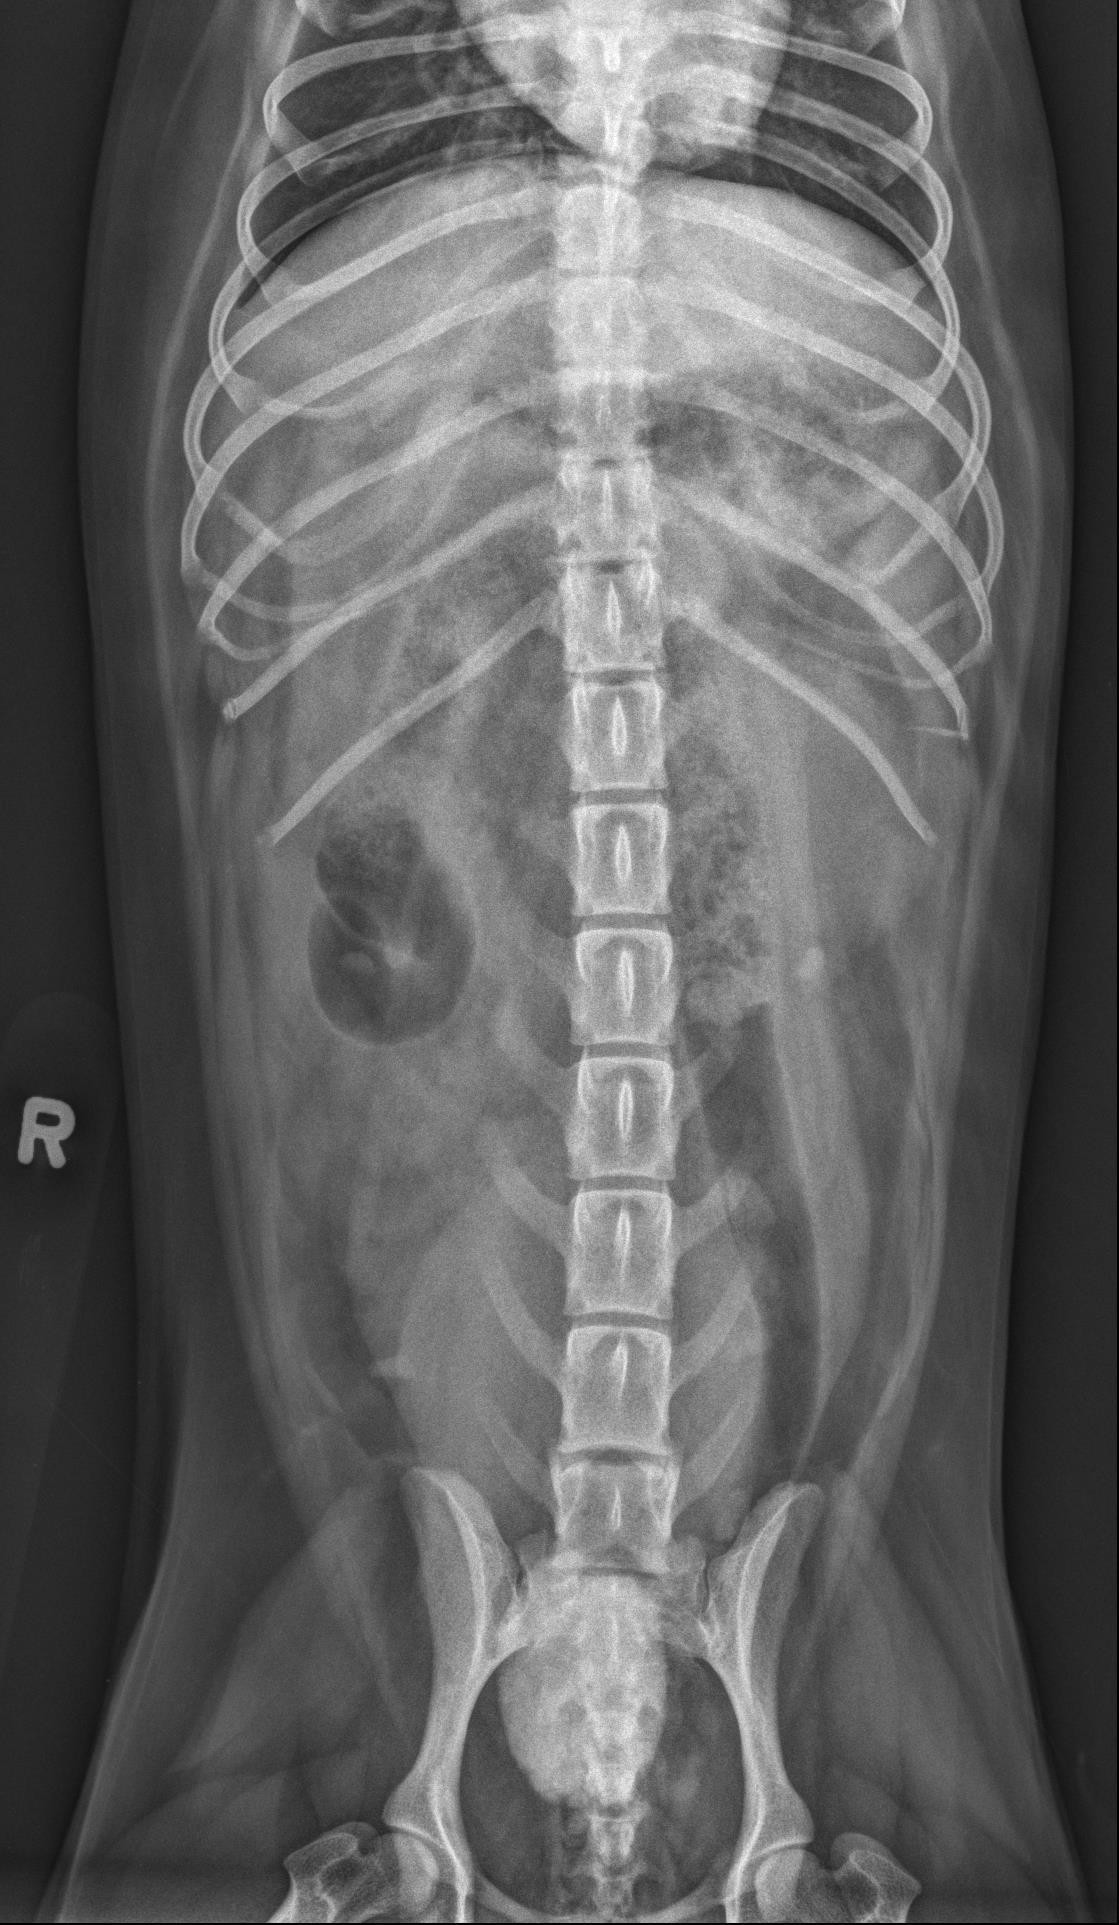

Hieronder vind je de 3 Röntgen foto’s van het abdomen. Gebruik de pijltjes om erdoor te schuiven, of klik op de foto om te vergroten.

Het retroperitoneale detail is aanzienlijk verminderd, met vloeistof-opaque strepen die de niergrenzen verdoezelen. Het peritoneale serosale detail is licht verminderd in de caudale buik, langs de craniale rand van de urineblaas.

Er is een grote, ovale, mineraal-opaque structuur net craniaal van de bekkenopening, in de regio van het trigonum van de urineblaas/proximaal van de urethra, met licht onregelmatige randen (3,6 cm in lengte en 2,5 cm in diameter). De urineblaas is matig tot sterk gedilateerd en homogeen vloeistof-opaque. De lever, milt en het maag-darmkanaal zijn normaal.

Het T8 wervellichaam is verkort en wigvormig.